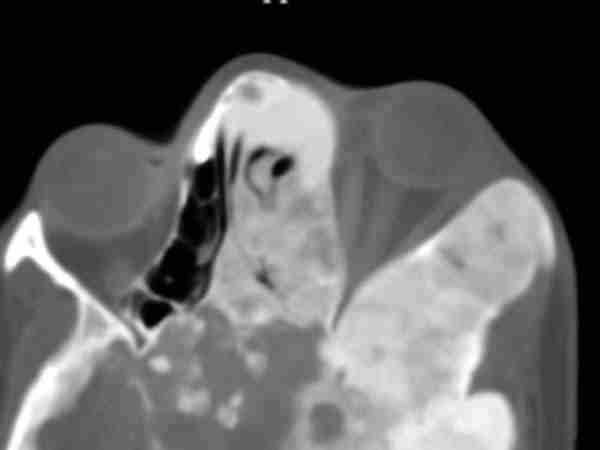

58-05.jpg (13167 bytes)

Figura 5. La imagen de TC muestra un neumoencéfalo en una fractura del techo de la orbita izquierda.